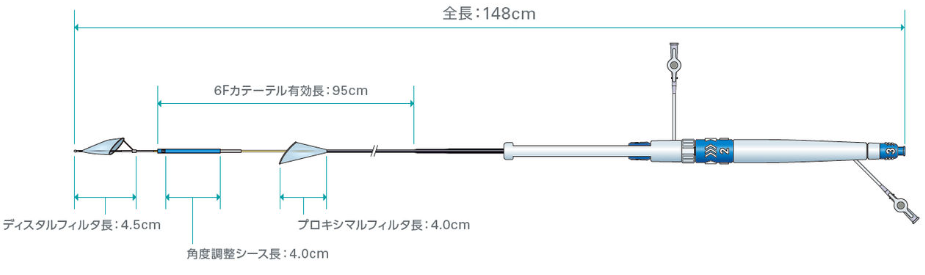

寸法:公称値

販売名:SENTINEL 脳塞栓保護デバイス

医療機器承認番号:30600BZX00150000

本製品は、TAVI手技中に腕頭動脈と左総頸動脈の入口部に一時的に フィルタを留置することで、脳卒中のリスクとなり得る弁尖や石灰化病変の組織片、心筋筋組織、血栓等の塞栓物質を捕捉、除去します。1つのサイズで留置する動脈の多様な解剖に対応しています 。また、これらの血管は脳への血流の主要経路を担っており、本製品のフィルタにより脳全体への血流の約90%を保護することで、TAVI手技中の塞栓物質による、術後の脳卒中リスクを低減できる可能性があります。

・右上肢からの直径2mm程度の細い管(6Fシース)による低侵襲なアクセス

・1つのサイズ、3つの操作でフィルタ展開が可能

②操作性

・独立したハンドルコンポーネントによりフィルタごとの操作が可能

・角度調整シースによる多様な左総頸動脈にも容易に到達